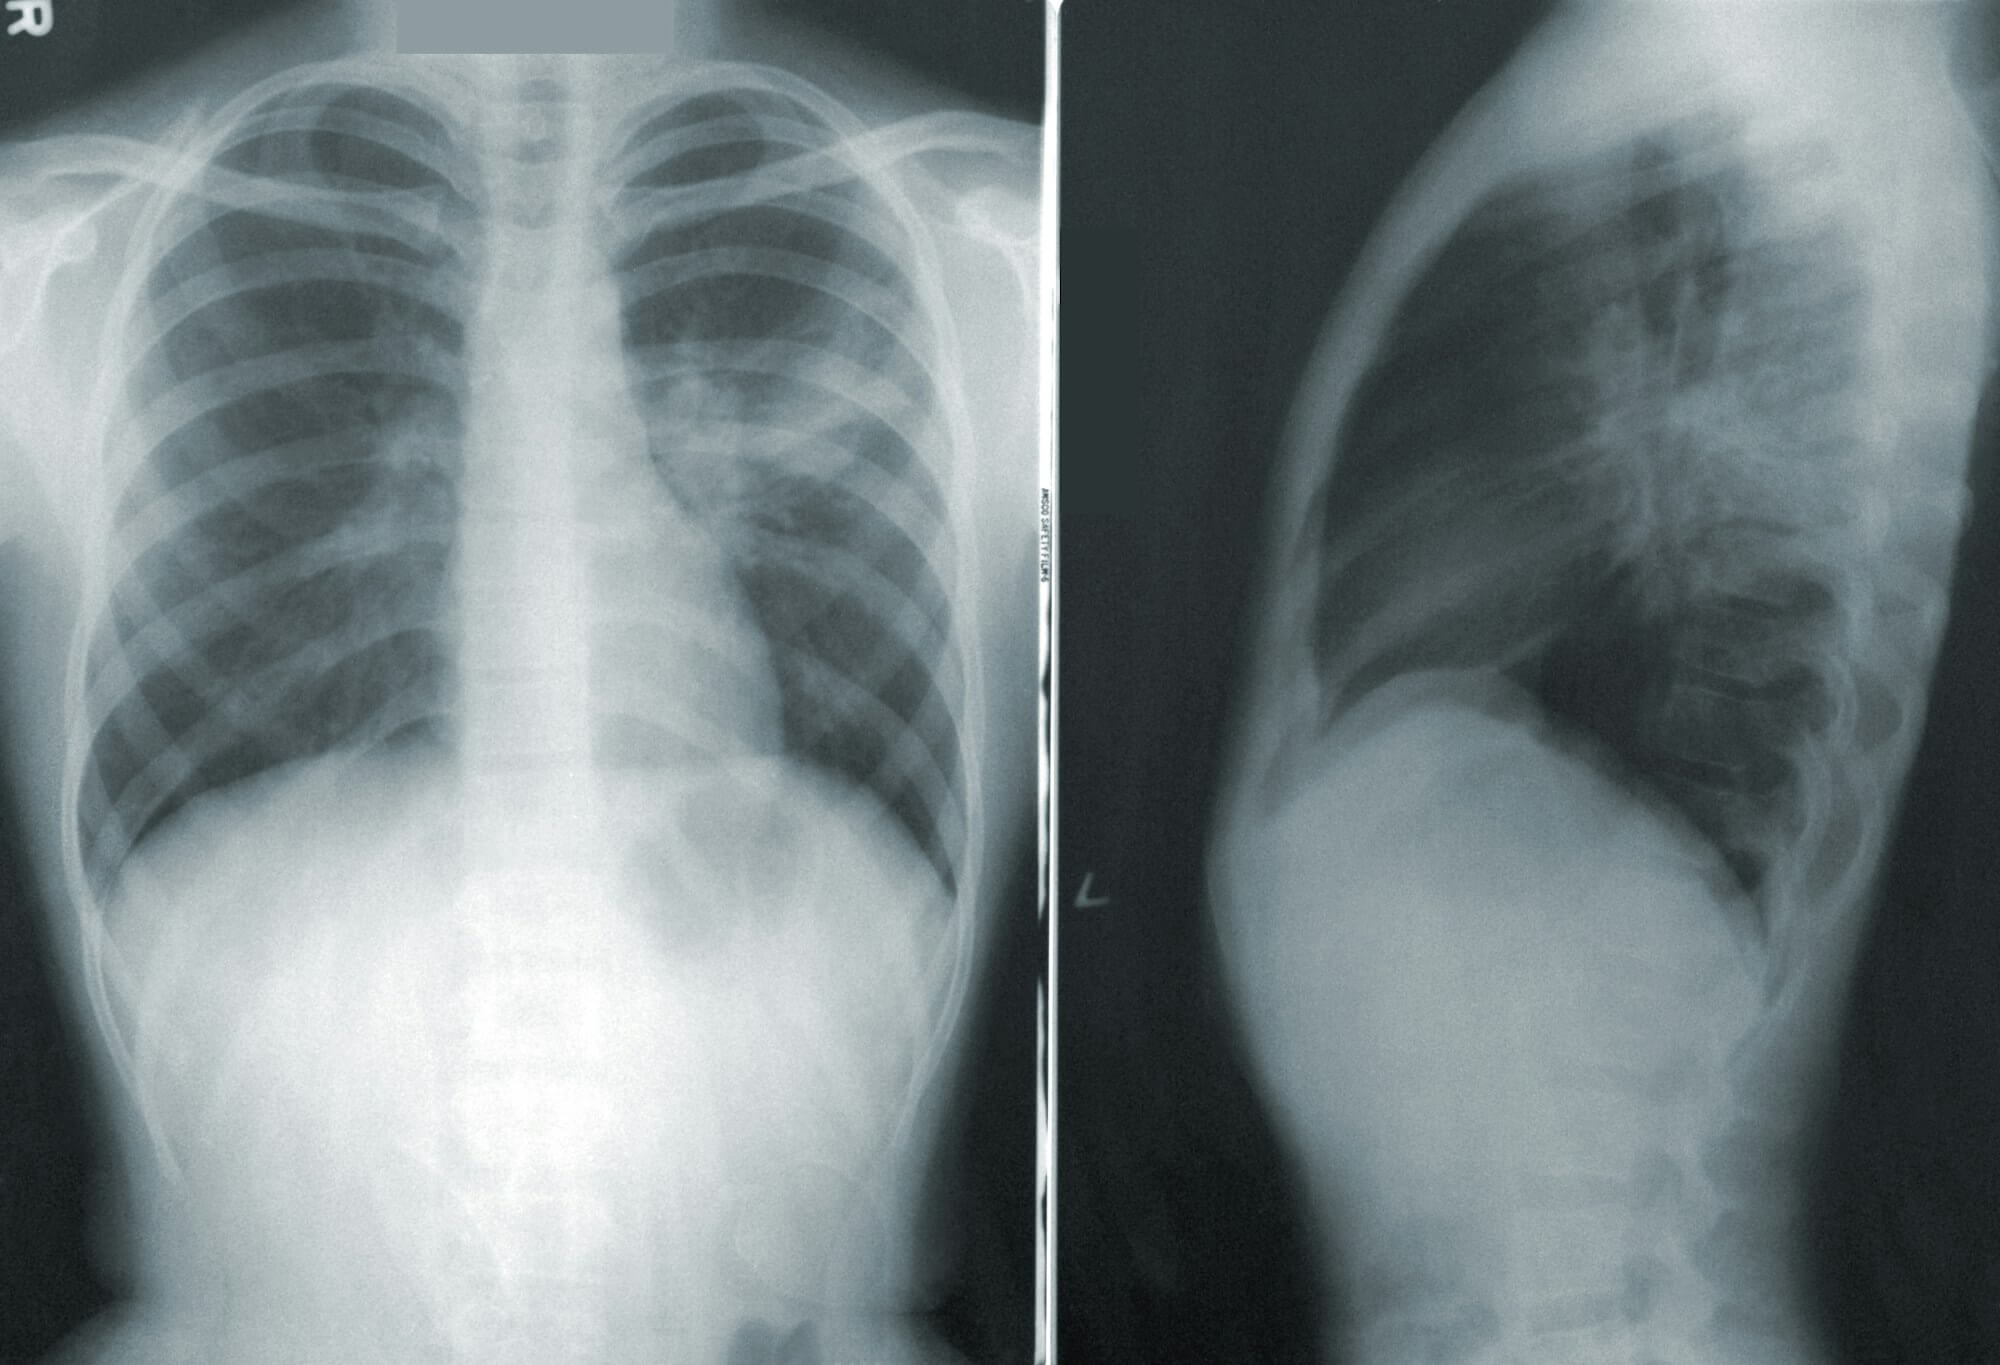

Long story short - the Doctor comes in and does a few breathing tests and wants me to get an X-ray to confirm Pneumonia. I walk down the hall into a different room and take some shots of my lungs and head on out of there with 2 prescriptions:

I'm told to await a call after a radiologist reviews the findings, but in the meantime both the prescriptions will help. They call a few hours later and confirm my lungs have the findings consistent with Pneumonia. I appreciate this validation because hitting like day 14 and unable to heal myself was a bit maddening.